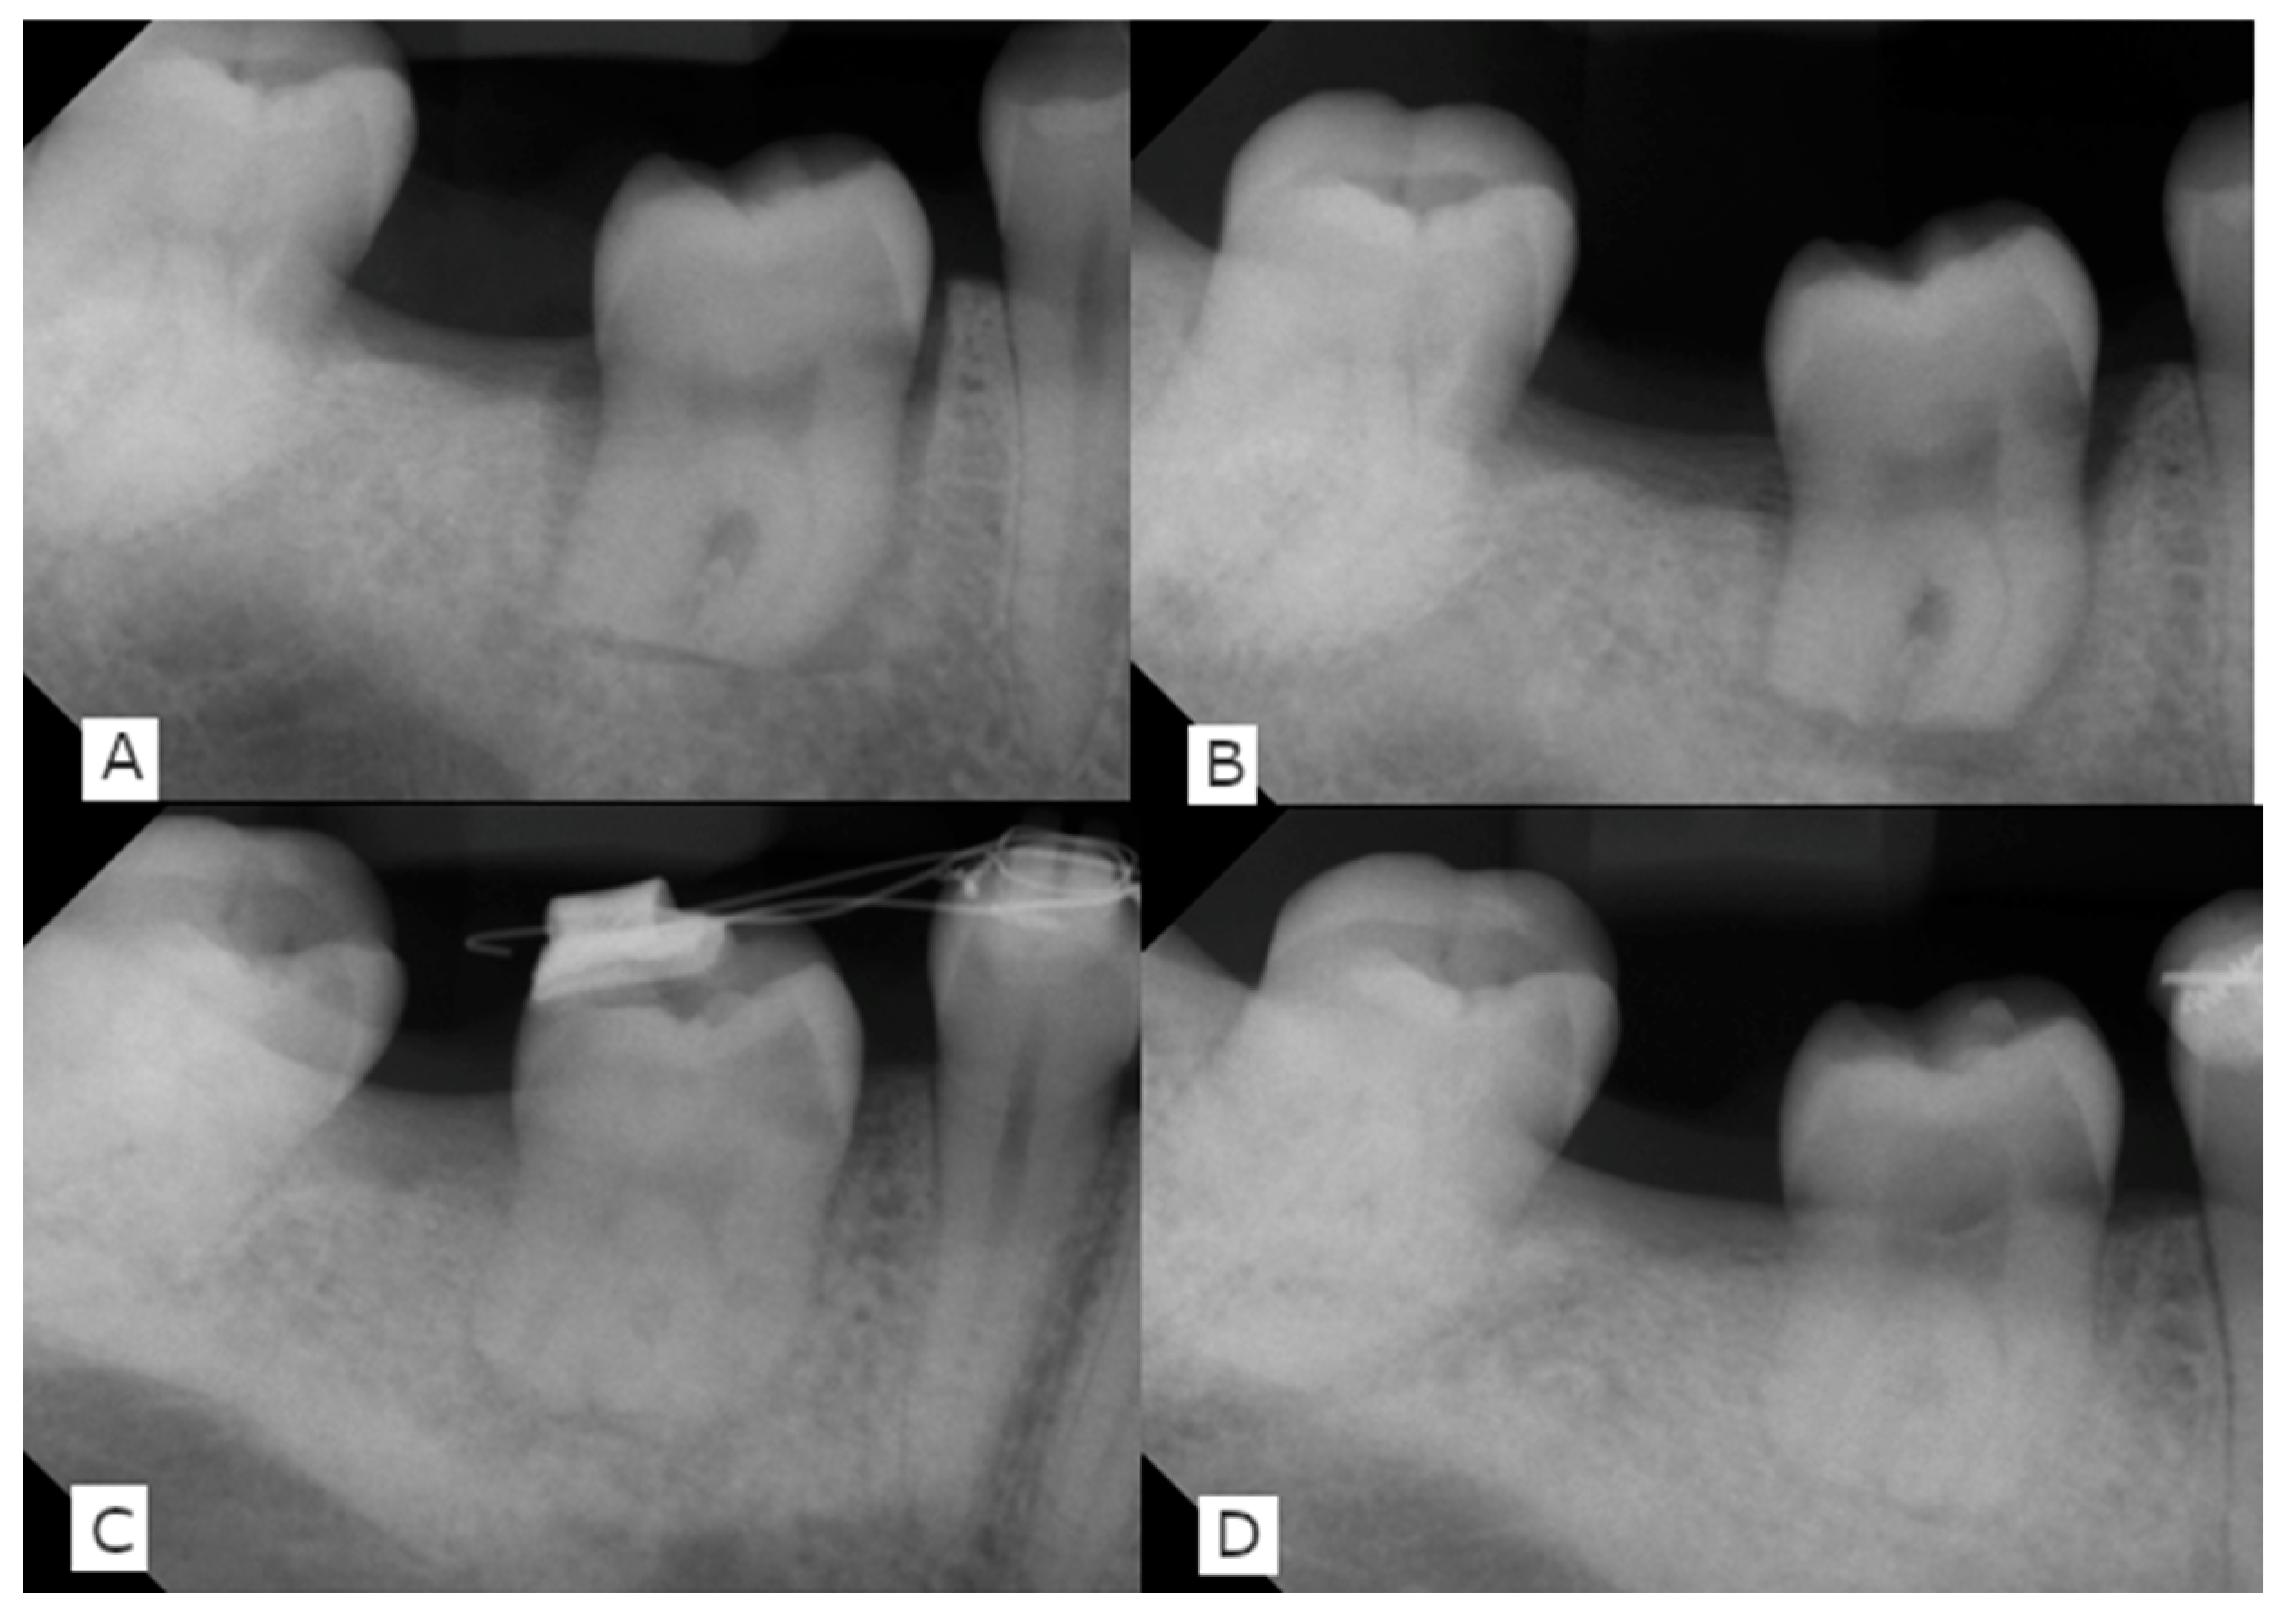

2. Report